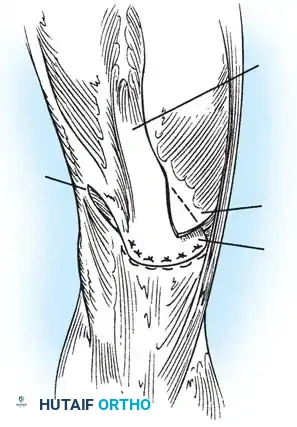

Fig. 45-16A: West and Soto-Hall technique. Following excision of the patella, a lateral release is performed. The vastus medialis is mobilized, and the quadriceps tendon is prepared for advancement over the patellar tendon defect.

Fig. 45-16B: The quadriceps tendon is drawn distally and sutured directly to the patellar tendon. The vastus medialis is then advanced distally and laterally, imbricating it over the midline repair to centralize the tracking vector and reinforce the extensor mechanism.

1. Excision: Carefully enucleate the patella from its tendinous envelope, preserving as much continuous retinacular tissue as possible.

2. Lateral Release: Perform a controlled lateral retinacular release to decompress the lateral compartment and allow for medial mobilization of the extensor mechanism.

3. Tendon Approximation: Draw the central quadriceps tendon distally and suture it securely to the proximal stump of the patellar tendon using heavy, nonabsorbable locking sutures.

4. Vastus Medialis Advancement: Mobilize the vastus medialis obliquus (VMO). Advance it distally and laterally over the primary repair site. This V-Y type advancement not only thickens the repair but restores the dynamic medial stabilizing force lost during patellectomy.